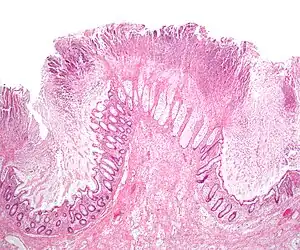

| A micrograph demonstrating cryptitis, a microscopic correlate of colitis. H&E stain. | |

An important investigation in the assessment of colitis is biopsy. A very small piece of tissue (usually about 2mm) is removed from the bowel mucosa during endoscopy and examined under the microscope by a histopathologist. It can provide important information regarding the cause of the disease and the extent of bowel damage.